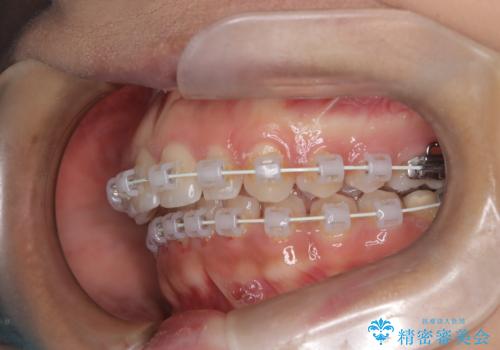

本症例では、非抜歯での治療を選択したため、スペースを確保するためにIPR(歯間削合)を行い、歯列を整えました。オーバージェット(上の前歯と下の前歯の水平的なズレ)は残る結果となりましたが、見た目や機能の改善を重視し、患者様と治療計画を共有しながら進めました。治療中は、歯列全体のバランスと噛み合わせを考慮しつつ、矯正装置の適切な使用を徹底しました。当初の計画通りに治療を完了し、患者様にも満足していただけました。

ワイヤー矯正の注意事項(リスク・副作用など)

- 治療中は違和感や痛みが起こることがあります

- 症状により、抜歯が必要な場合があります

- 治療中は歯磨きがしにくくなるため、虫歯や歯周病になりやすくなります